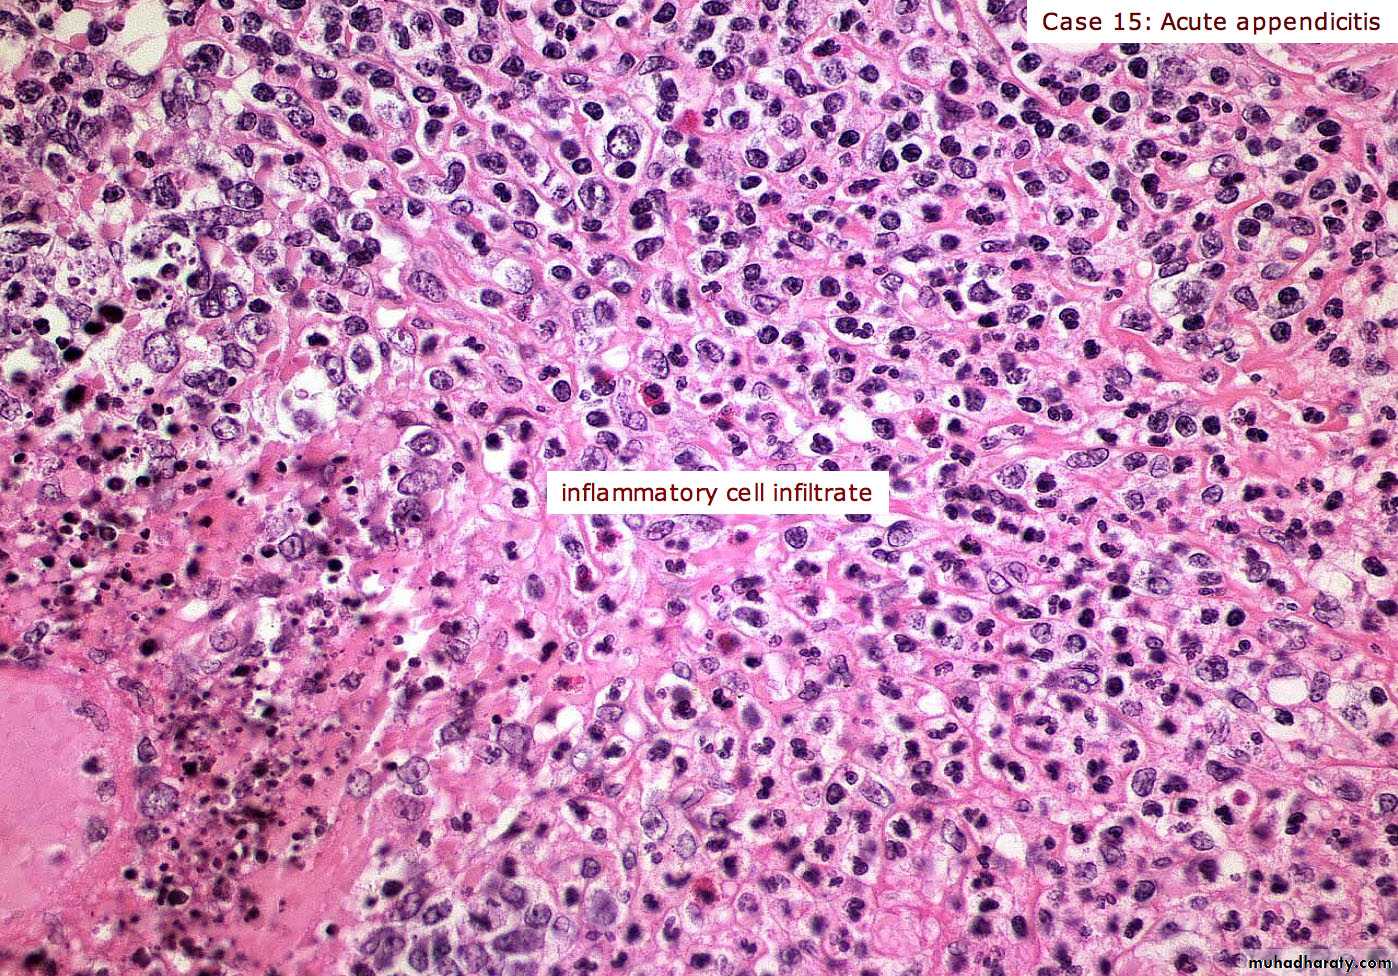

Acute appendix

Acute Inflammation